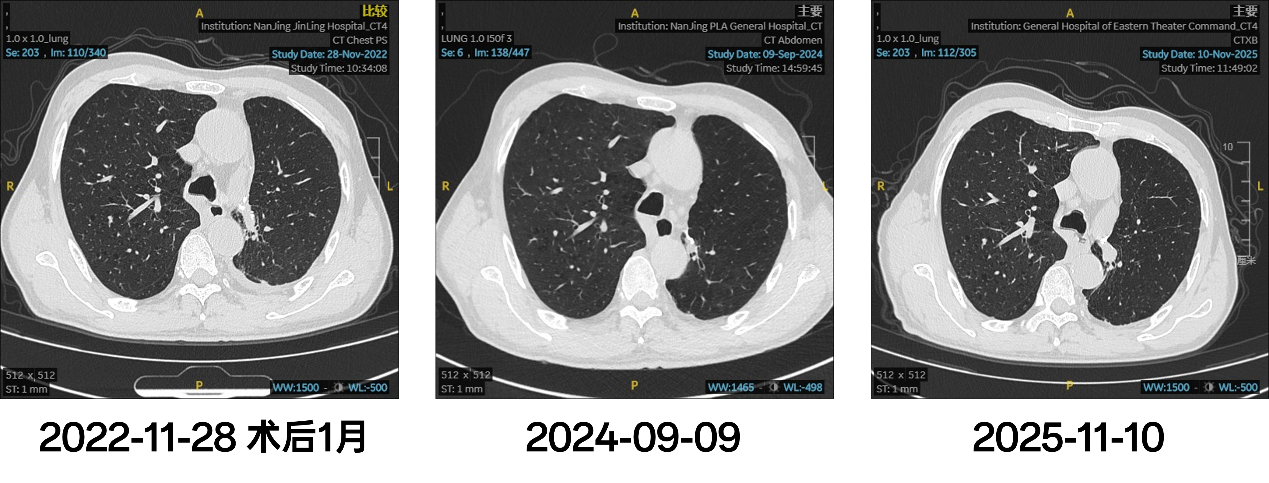

2年赠药结束后,患者因经济原因未继续维持治疗,定期复查,未见进展。

图4. 术后随访影像

患者接受“夹心饼式”新辅助+辅助围术期免疫治疗,在术前通过2周期新辅助治疗成功达到PR,术后继续治疗2周期后免疫单药维持治疗2年,至今保持定期随访,仍未见复发,目前无事件生存期(EFS)已超36个月。